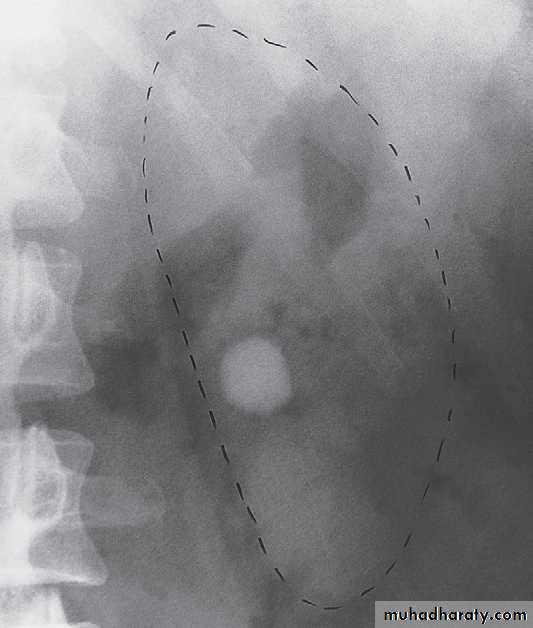

-Plain film in intravenous urogram: it used to Identify all calcifications. Decide if they are in the kidneys by relating them to the renal outlines , calcification seen in the line of the ureters or bladder must be reviewed with post contrast scans, to determine whether the calcification lies in the renal tract. Note that calcification can be obscured by contrast medium and stones are missed if no plain film is taken.-Films taken after injection of contrast medium Kidneys

1 .Check that the kidneys are in their normal positions . The left kidney is usually higher than the right.2 .Identify the whole of both renal outlines. If any indentations or bulges are present they must be explained.